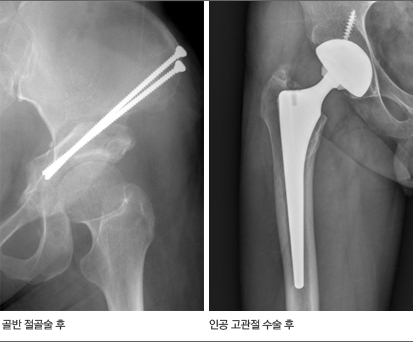

치료

우선적으로 약물과 물리 요법으로 치료한다. 약제는 일반적인 소염진통제를 기본으로 하며, 원인 질환에 따라 다른 약제를 추가로 투여한다. 화농성 고관절염에는 항생제를, 결핵성 고관절염에는 항결핵제를 투여하는데 이들의 경우 수술적으로 배농과 관절 세척을 필요로 하는 경우가 많다. 비구 이형성증이나 레그-깔베-퍼테스(Legg-Calve-Perthes) 병, 혹은 소아기 감염성 관절염으로 인해 고관절이 변형되어 퇴행성 고관절염이 생겼으나 아직 관절이 많이 손상되지 않은 경우에는 증상을 완화시키고 퇴행성 변화를 늦추기 위해 골반골이나 대퇴골을 절골(부러뜨림)하여 모양을 맞추어 주는 절골술을 시행할 수 있다. 어떤 원인에 의해 발생하든 고관절염이 진행되면 관절이 상당히 손상된다. 약물과 물리 치료를 하여도 일상 생활에 큰 지장을 받는 상태가 되면 인공관절 수술을 시행하게 된다.

고관절염 치료 후 X선 영상